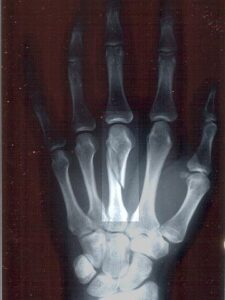

With some help from the Department of Defense, researchers at the University of Pittsburgh are fast-tracking development of something called “bone cement.” And by “help,” I mean $12 million in additional funding. According to Wired, Dr. B.J. Costello, the lead researcher, expects to have the technology in clinical human trials in the next 12 months to 2 years:

Costello, whose program involves the creation of an injectable compound designed to repair cranio facial bone damage or spur normal bone growth, expects to start trials on 20 patients, most of them veterans, within a year. If those trials go well, they’ll expand to test more people or explore using the cement for different, more serious procedures.

“Right now, we’re looking at mild to moderate injuries,” he said. “But eventually this could treat long bone injuries, or have civilian applications.”

And those applications would be widespread. The bone cement could replace metal plates, repair bone damage from car accidents or assaults, and even regrow entire portions of a human skull.